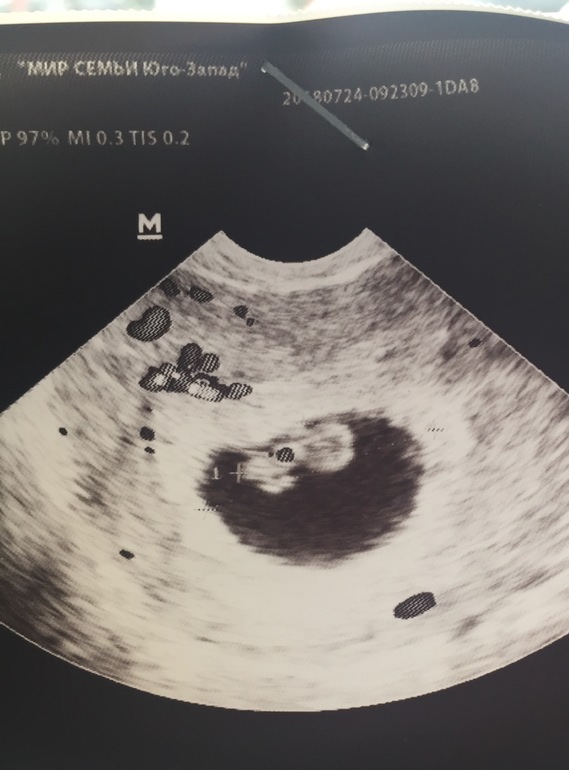

Первое фото , ничего интересного, просто плодное яйцо в матке , это 10 день задержки. А вот второе фото - на 24 день задержки - уже и малышика хорошо видно и сердечко слышаться ) Так что лучше дождаться хотя бы 20 дней и уже идти смотреть все в целом :)